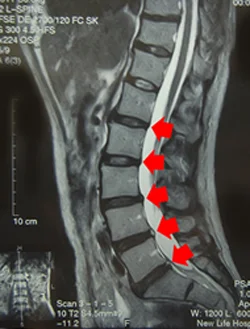

65歳男性(中心性脊髄損傷)

バレーリュー症候群モアレ

ヘッドレストのない車に乗車中、衝突されて負傷しました。一か月入院した後に当院へ来院されました。肩甲骨が麻痺により浮いているのが分かります。手の知覚異常と筋肉の衰えを治すのに鍼治療が効果的でした。

脊髄は、急激に振られると中心の繊維を痛めます。脊髄の中心には手の知覚を脳に運ぶ神経線維があるので、手の知覚異常を主体とした症状が出ます。コンタクトスポーツや自動車事故に多いむち打ちです。